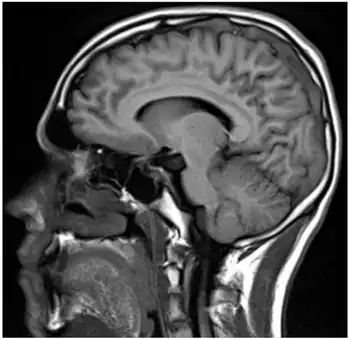

Sagital-Prothrombin G20210A as cause of cerebral venous thrombosis